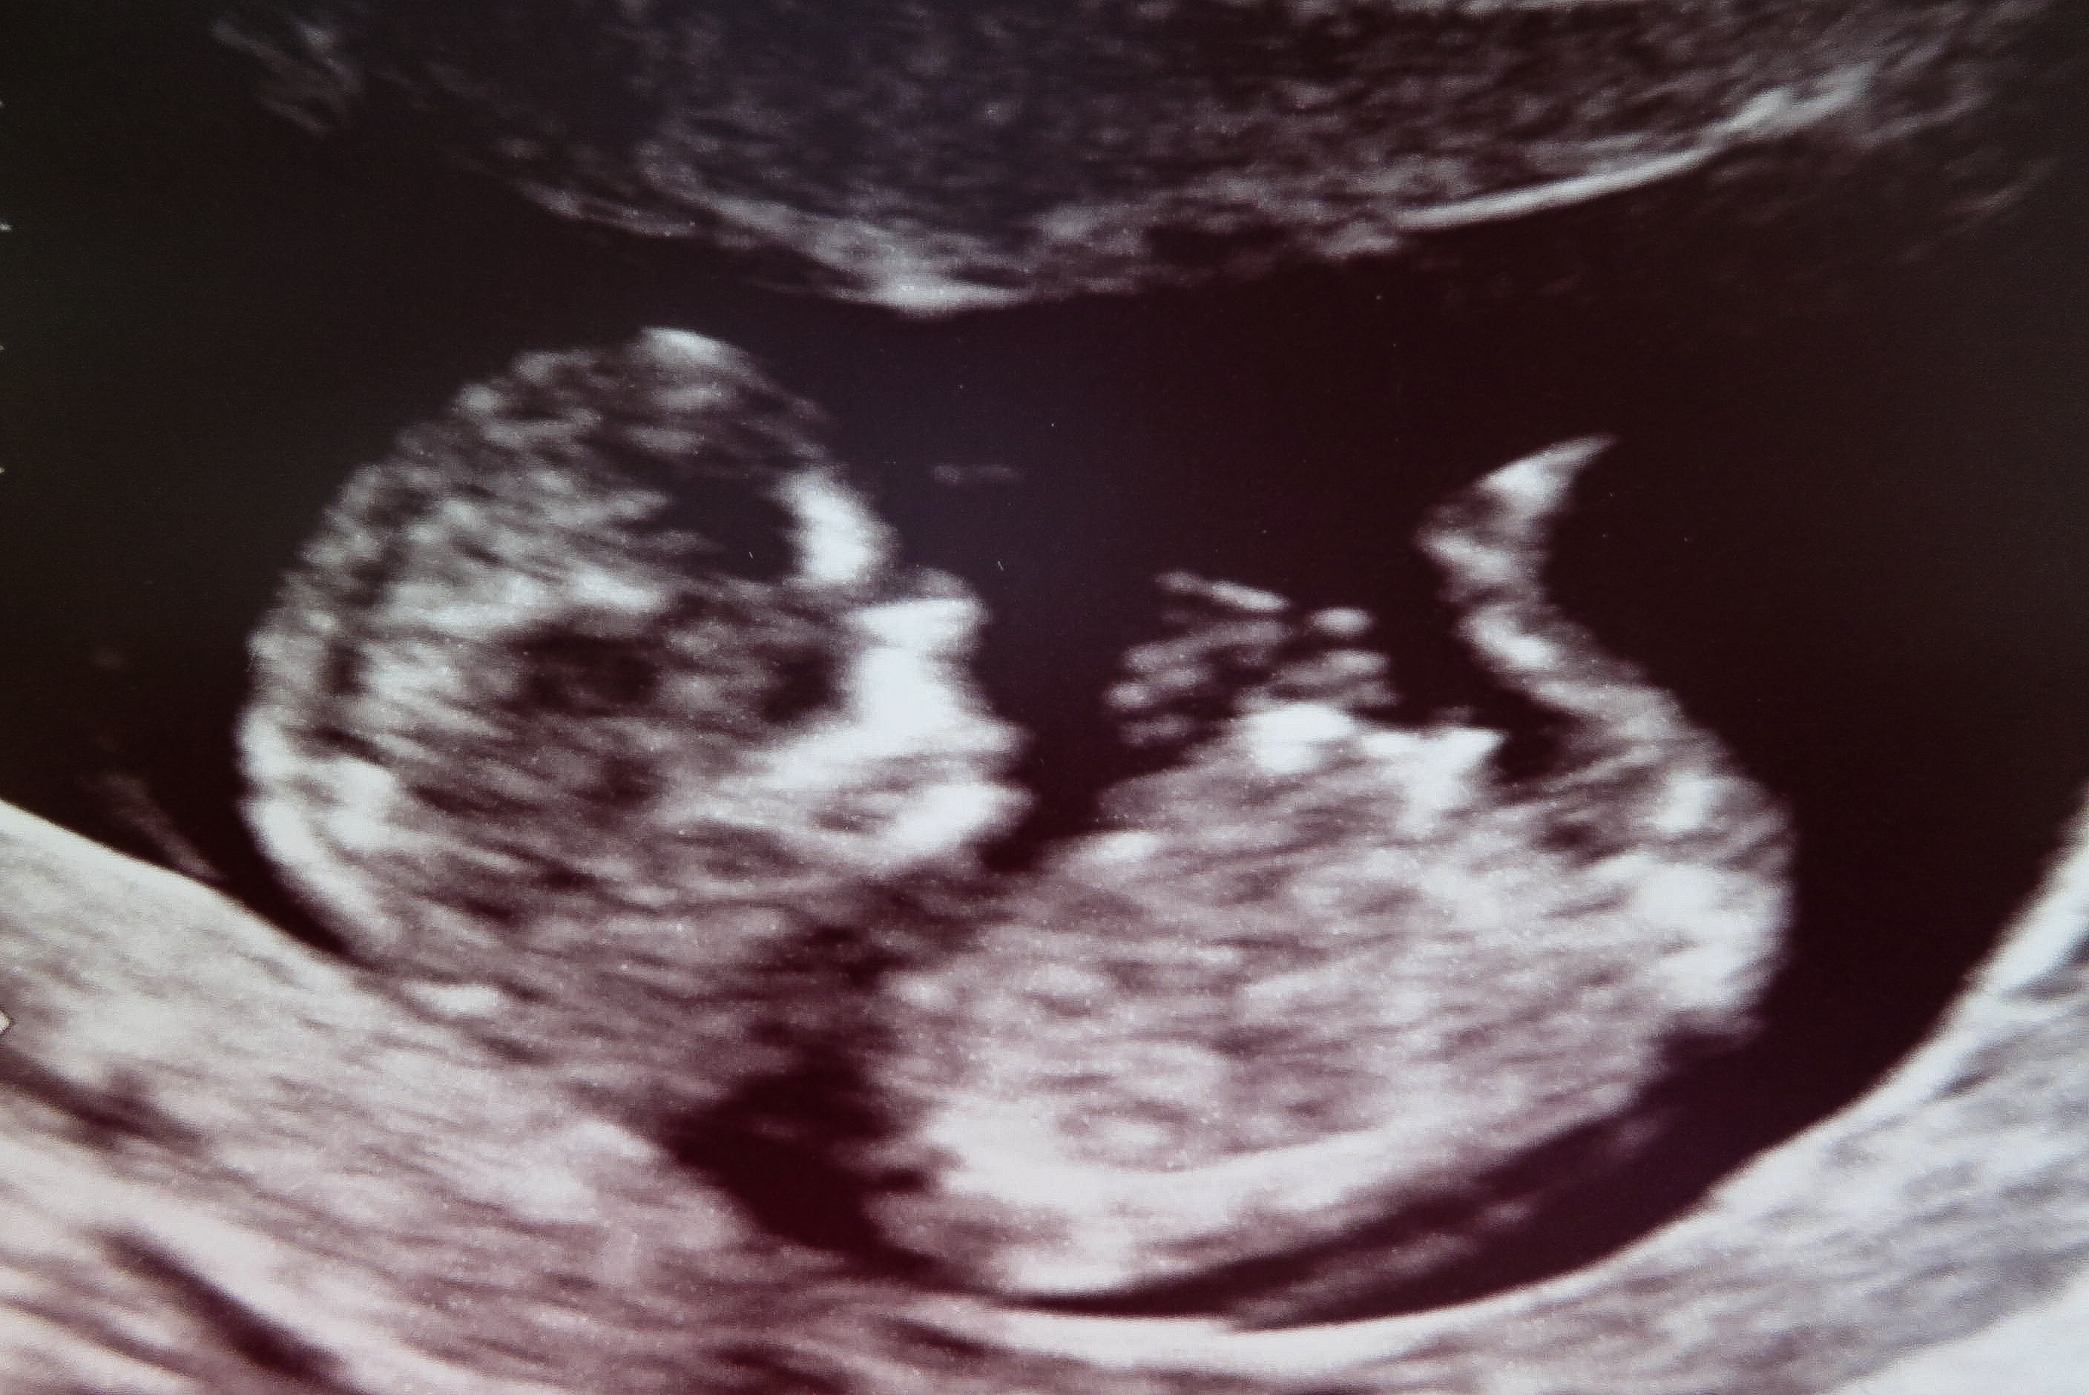

Had our 12w5d ultrasound today. Baby is thankfully healthy and measuring 12w3d.

Any guesses based on nub or skull theory? Thanks, mamas!

and this last one (the tech gave to my older son) I just noticed has a boyish nub, but not sure if I am seeing the cord lining up just so to make it seem like a boy nub, or if it really is looking blue.